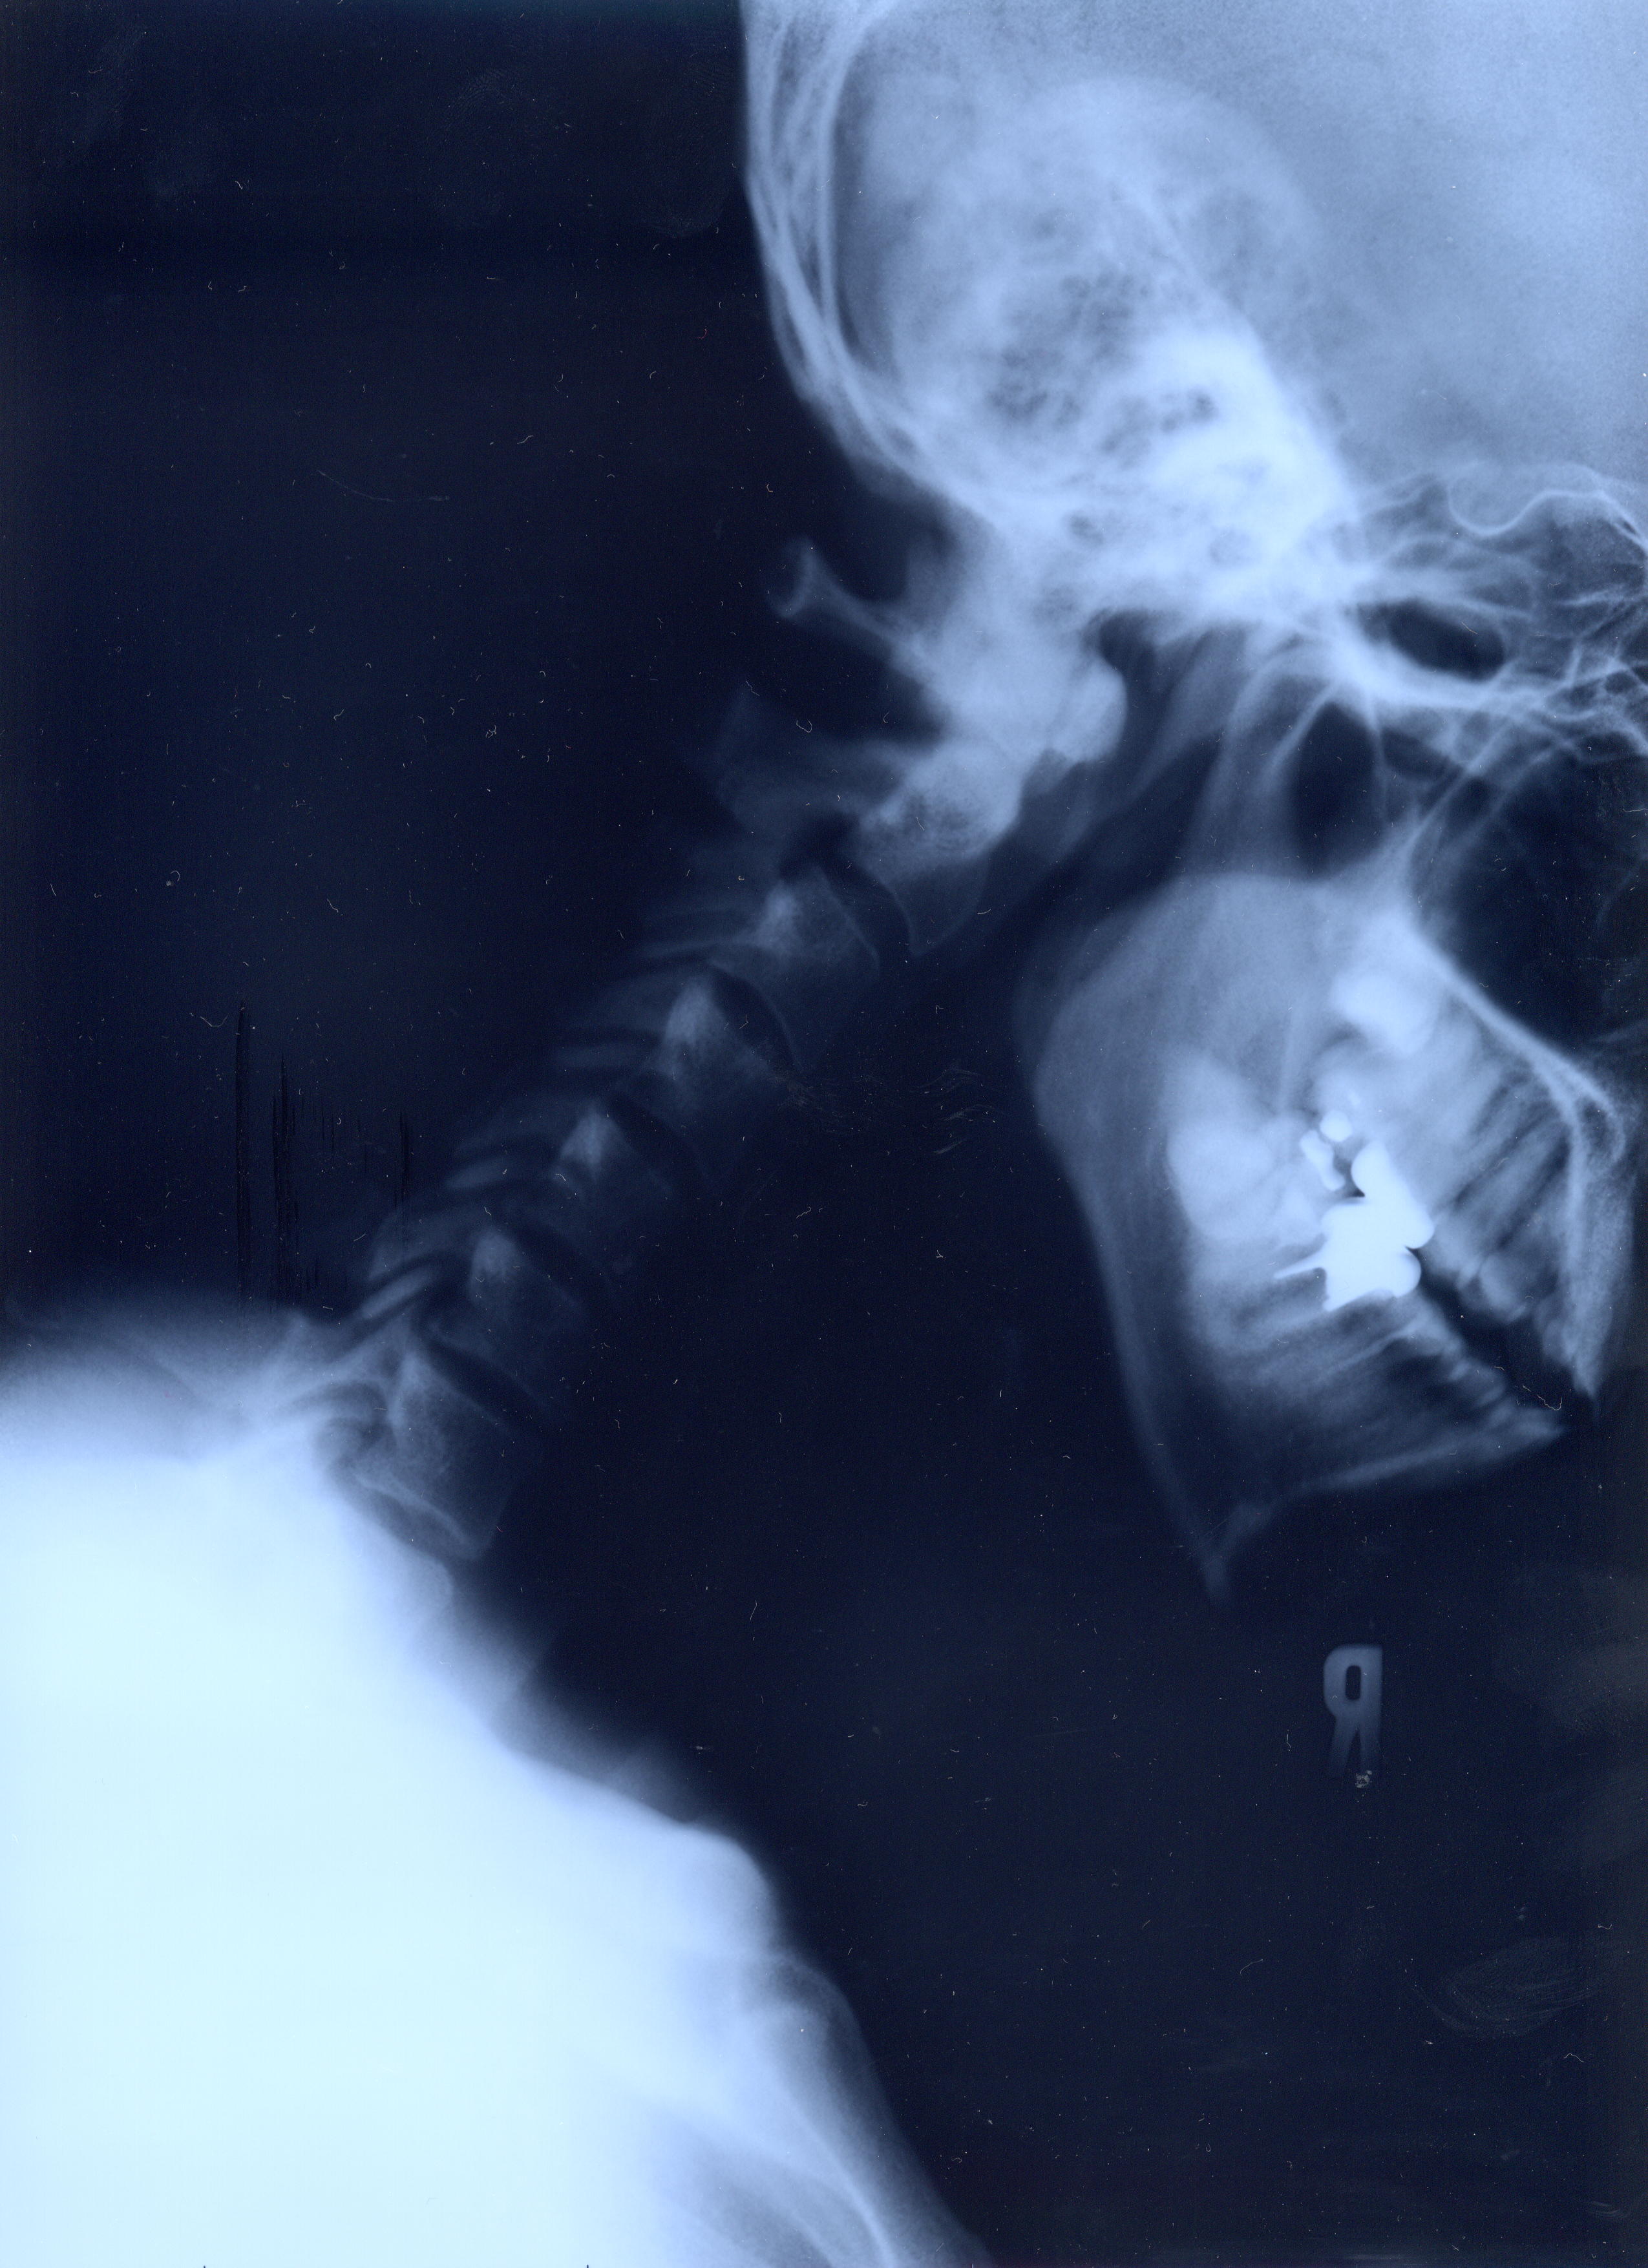

@@Ž„‚Μ”wœ‚Μ‚wόŽΚ^‚Ε‚·@@˜‚ͺ’Ι‚­‚Δ’Ι‚­‚āII@2002/1/22ŽB‰e

‚PD˜‚̐³–ʁ@ @@Šg‘ε